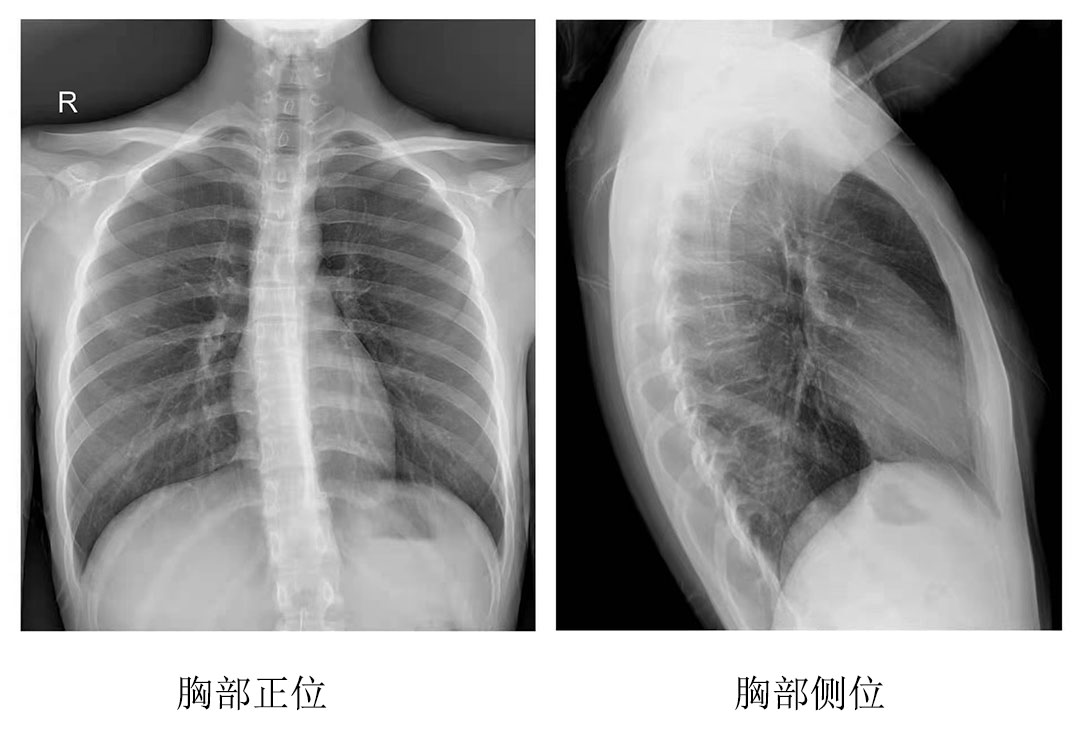

為其中一位年長的患者完成拍片工作后,操作醫師表示:今天為這位年長的患者服務時,動態平板DRF的床體升降和腳踏板360度旋轉功能很實用,上下床非常方便。不但減輕醫護人員的負擔,也縮短了患者的檢查時間,拍出來的圖像很清晰,對拍片成果很滿意。